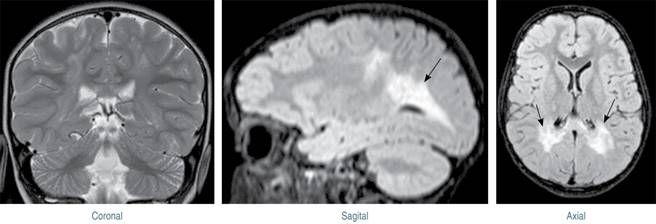

Al ingreso en el centro, se identifica que tiene tratamiento con prednisona y melatonina. Además presentan las imágenes de una resonancia magnética de cráneo que muestran afectación de forma bilateral de la sustancia blanca periventricular de los lóbulos parietal y occipital, incluyendo el trayecto de la vía piramidal, a través del brazo posterior de las cápsulas internas y mesencéfalo (Figura 1).

Figura 1: Imagen de resonancia magnética craneal, cortes coronal, sagital y axial donde se observa la desmielinización occipital y parietal.

En la enfermedad de Krabbe existe acumulación de galactocerebrósido y psicosina. El aumento de la psicosina tiene un efecto tóxico en los oligodendrocitos y afecta a la producción de la mielina, causando desmielinización progresiva tanto del sistema nervioso central como del periférico.15 En la Figura 1 se observa una clara desmielinización de la región parieto-occipital, con un rol fundamental en el procesamiento visoespacial: la desmielinización posterior con la que suele cursar la enfermedad de Krabbe es la responsable de la agnosia visual aperceptiva que presenta nuestro paciente, que le impide copiar dibujos. En otro caso descrito en la literatura se informa de agnosia visual asociativa, con una discrepancia entre aspectos intelectuales verbales y manipulativos no tan grave como la de nuestro paciente, ya que no presentaba desmielinización tan avanzada.3,16 Algunos autores han sugerido que las formas aperceptiva y asociativa de la agnosia se diferencian por la gravedad de las alteraciones perceptivo-visuales,11 las cuales pueden formar parte de un continuo más que patologías distintas.